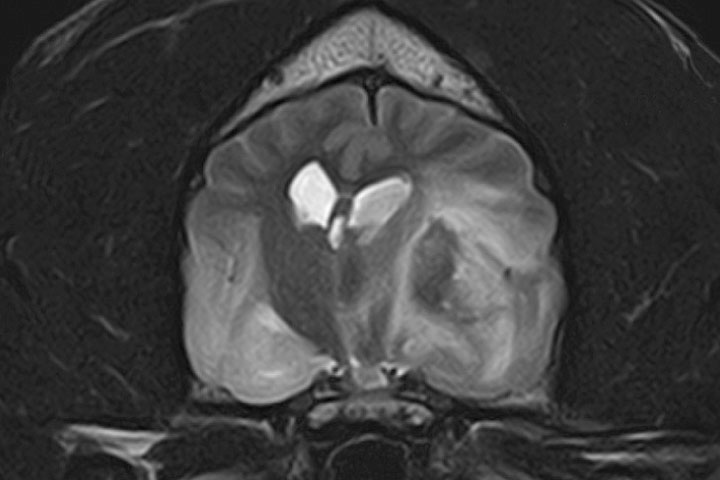

Gliomas are the second most common primary brain tumour in dogs. They are more prevalent in brachycephalic breeds, but rare in cats.

On MRI they appear as intra-axial masses with mass effect and heterogeneous contrast uptake. Some can have accompanying signs of haemorrhage (T2* signal void).

Gliomas can be divided histopathologically in oligodendrogliomas and astrocytomas, with different grades of malignancy; from slow growing to highly aggressive glioblastoma multiforme or gliomatosis cerebri.